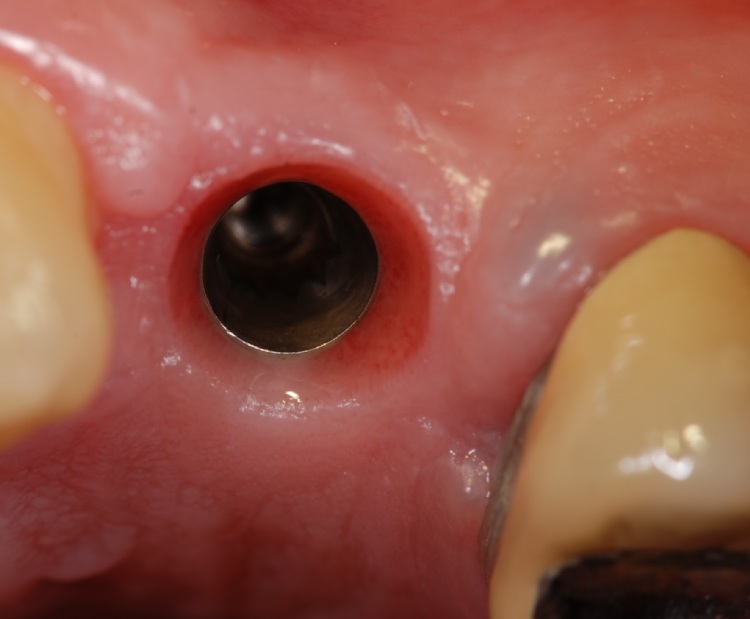

Il paziente si è presentato in studio per una frattura della radice di 2.4, già riabilitato protesicamete con perno fuso. L'intervento ha comportato l'impiego contestuale di osso sintetico e fattori di crescita (PrGF)